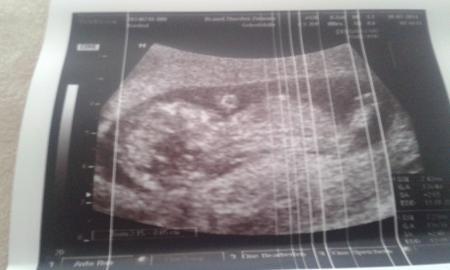

...und ich bin erleichtert und grinse wie ein Honigkuchenpferd... Dem Käfer geht es gut und ist jetzt 7,4 cm groß. Das heißt 10 Tage weiter, aber ET wurde nicht geändert. Herzchen schlägt kräftig, es hat gestrampelt und gewunken. Nächster Termin ist am 05.08.14...

Hier das Bildchen ♡♥

Bild zu